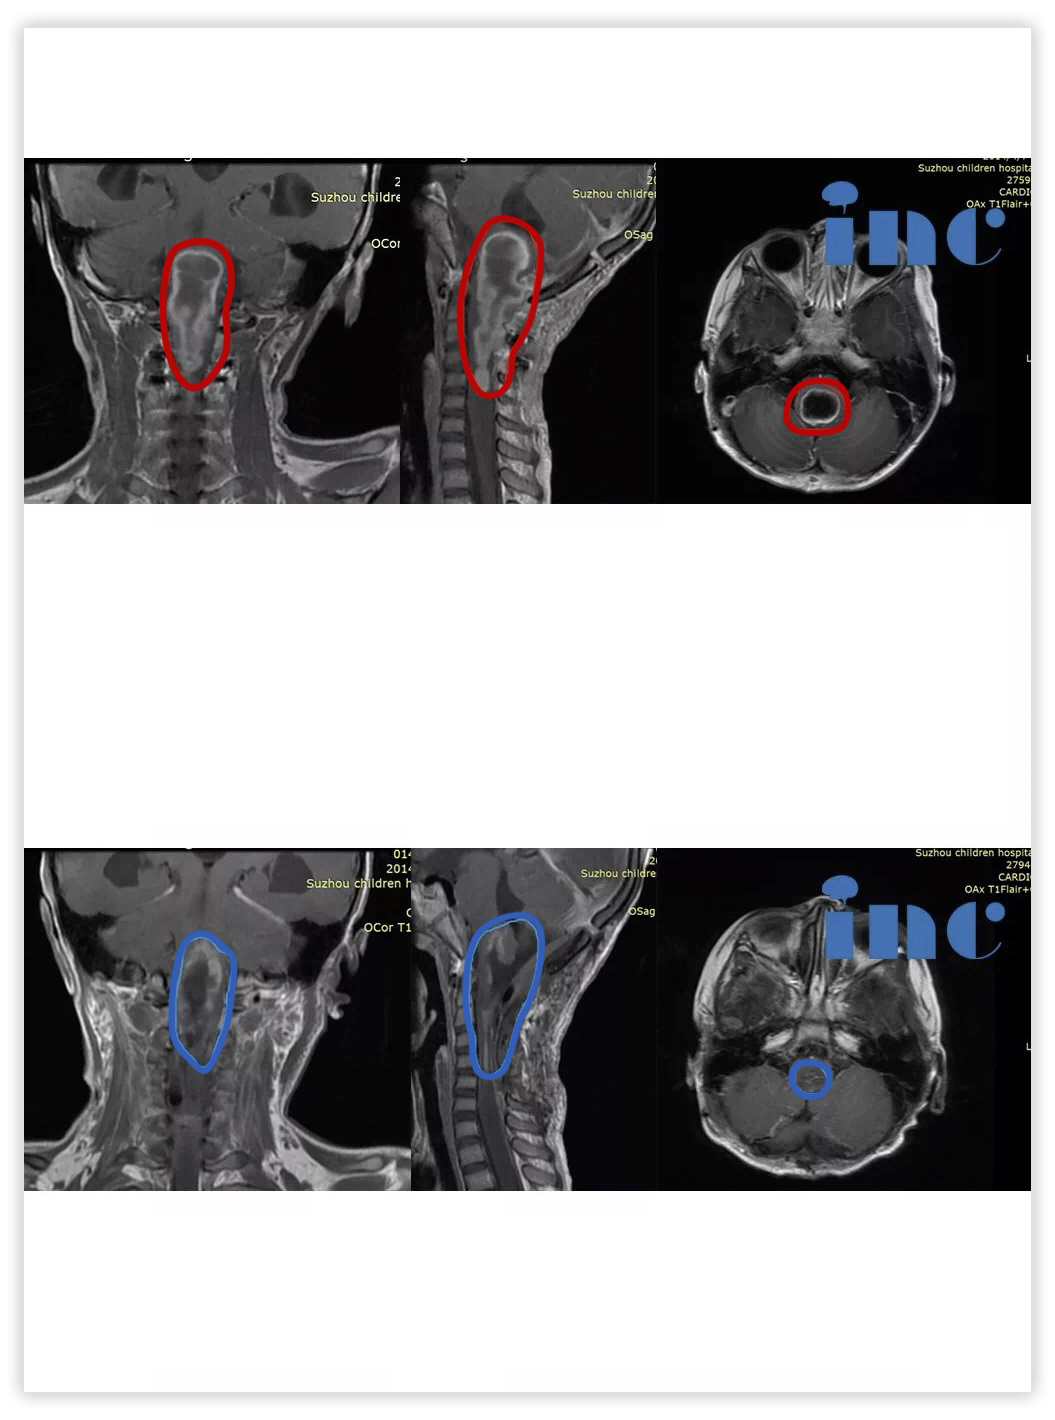

6岁男孩-延髓毛细胞星形细胞瘤

术后两个多月,天天行走自如正常回归学校。